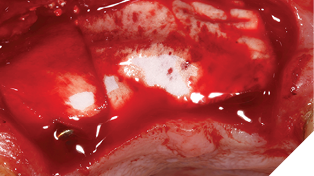

The autogenous bone chips collected were applied to any exposed implant threads and Cerabone was then placed buccally to reinforce and increase hard tissue volume. Jason membrane was used to cover the augmented region and further periosteal relieving incisions were made to ensure tension free closure.

The surgical site was closed with a series of simple interrupted Vicryl Rapide sutures for ease of patient comfort and convenience (Figs. 19-21).